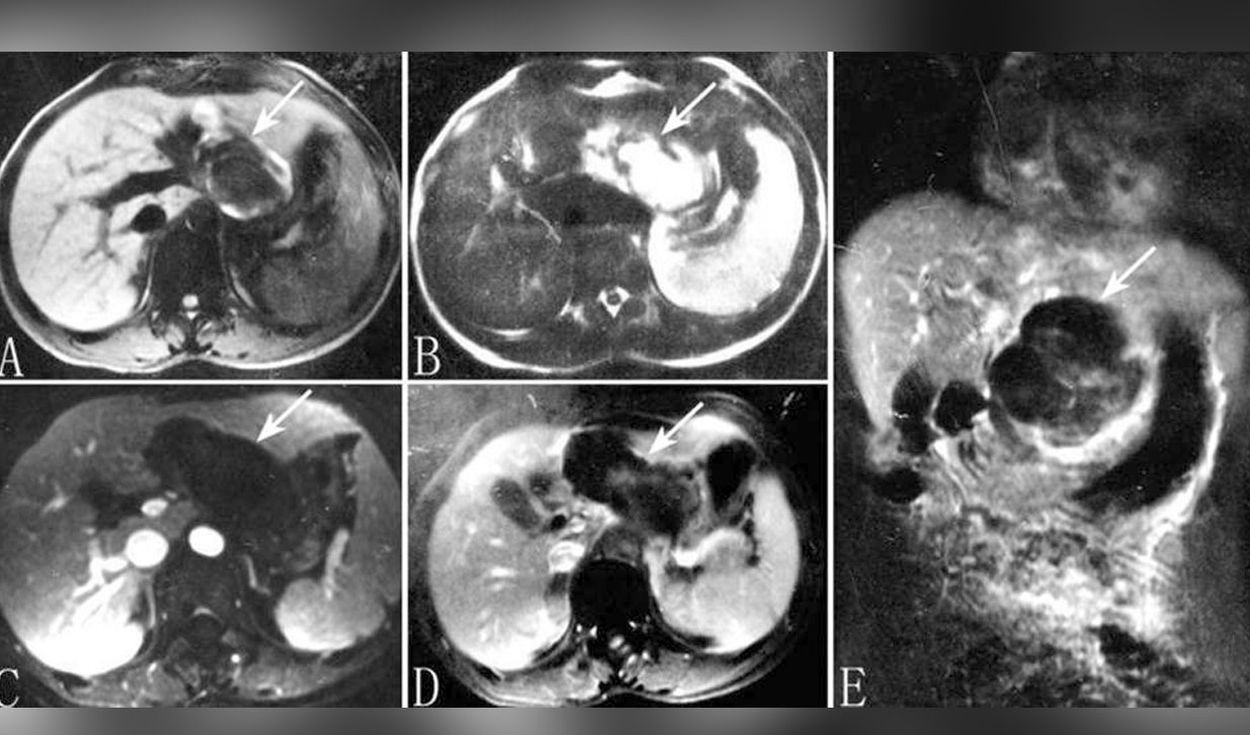

Entonces se procedió a hacerle un ecografía que reveló que había un bebé en su hígado.

Tenía una versión extremadamente rara de un embarazo ectópico, en el que "un óvulo fertilizado se implanta y crece fuera de la cavidad principal del útero", de acuerdo con los datos de la Clínica Mayo.

Sin embargo, el caso de esta paciente era aún más raro, ya que el embrión "acabó viajando hasta el hígado, donde se implantó", señaló el médico.